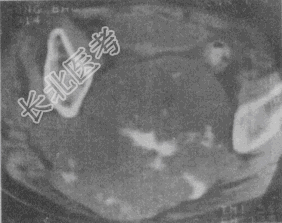

- 单项选择题男性,55岁, 骶尾部疼痛1年,近2个月来大便困难。CT片如图。应首先考虑的诊断是

A、骨转移瘤

B、骨髓瘤

C、脊索瘤

D、骨淋巴瘤

E、神经纤维瘤